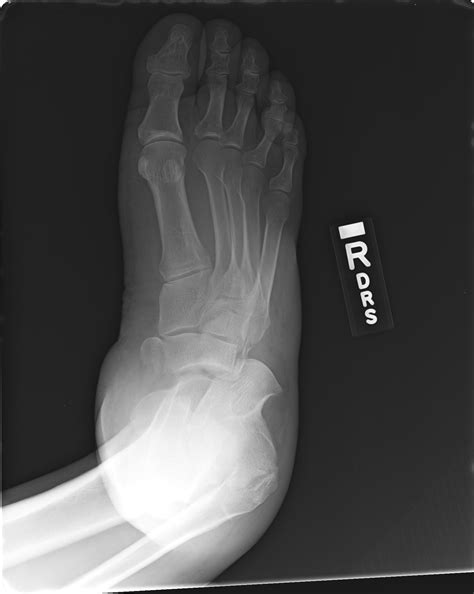

FOOT FRACTURE - Buyxraysonline

FOOT FRACTURE - Buyxraysonline